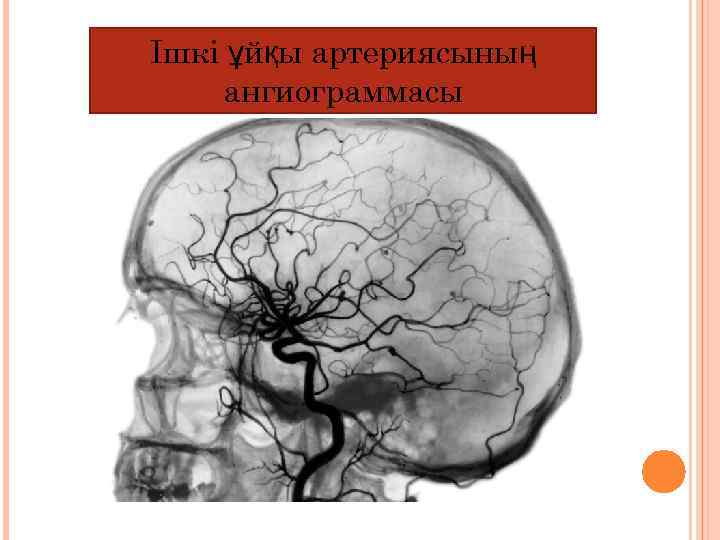

Церебральды ангиография (бас ми ангиоартериялары) аневризмаларды анықтау үшін , гематома, ісіктерді, тамырлардың стенозы және тромбозы. Мидың үлкен жарты шарларының патологиясында қолданылады.

Ішкі ұйқы артериясының ангиограммасы